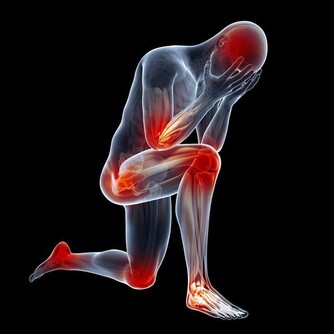

有「帝王病」之稱的痛風,是現代人常見的文明病之一,

引發原因大多為患者飲食過於豐富,經常大魚大肉,導致人體內尿酸生成過多,形成「高尿酸血症」。

進而形成尿酸鹽結晶,沉積在關節內,造成關節疼痛及腫脹。